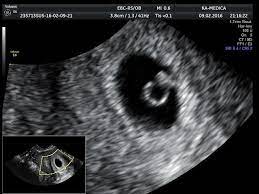

pęcherzyk bez zarodka

witam dziewczyny , wczoraj byłam u ginekologa z badań usg wychodzi ze jestem w 5 tyg ciąży. Na usg pokazał się tylko pęcherzyk bez zarodka. koleją wizytę mam w pon 15 . Kiedy może pojawić się zarodek? Czy czesre badanie usg może zaszkodzić maleństwu?

@Danuś 91 Niestety dowiesz się dopiero na wizycie. Może być tak, że się pojawi. a może się nie pojawić. Skoro jest już pęcherzyk, to wróży to dobrze, więc zarodek powinien się pojawić. W sumie moim zdaniem powinnaś mieć wizytę po 2 tygodniach, bo 15 nawet jak będzie zarodek, to niekoniecznie będzie echo serca i znów będziesz się stresować.

Myślicie że to mógłby być zarodek? Ten młody ginekolog powiedział że ciąża jest młodsza.

Waszym.zdaniem to może być zarodek?

Ja myślałam że jestem ca. 6t3d bo tak mi wskazywały apki. Owszem cykle mam nieregularne grudniowy trwał 375 dni A styczniowy 35. Wczoraj byłam.w medicover i jedyna nadzieja że sprzęt mają fatalny.Myślicie że to mógłby być zarodek? Ten młody ginekolog powiedział że ciąża jest młodsza.

Waszym.zdaniem to może być zarodek?Zobacz załącznik 1246491

Zdjęcie USG wygląda mniej więcej w ten sposób (pierwszy wynik z wyszukiwarki). Szczerze mówiąc pierwszy raz widzę takie zdjęcie jak u Ciebie 🤷‍♀️